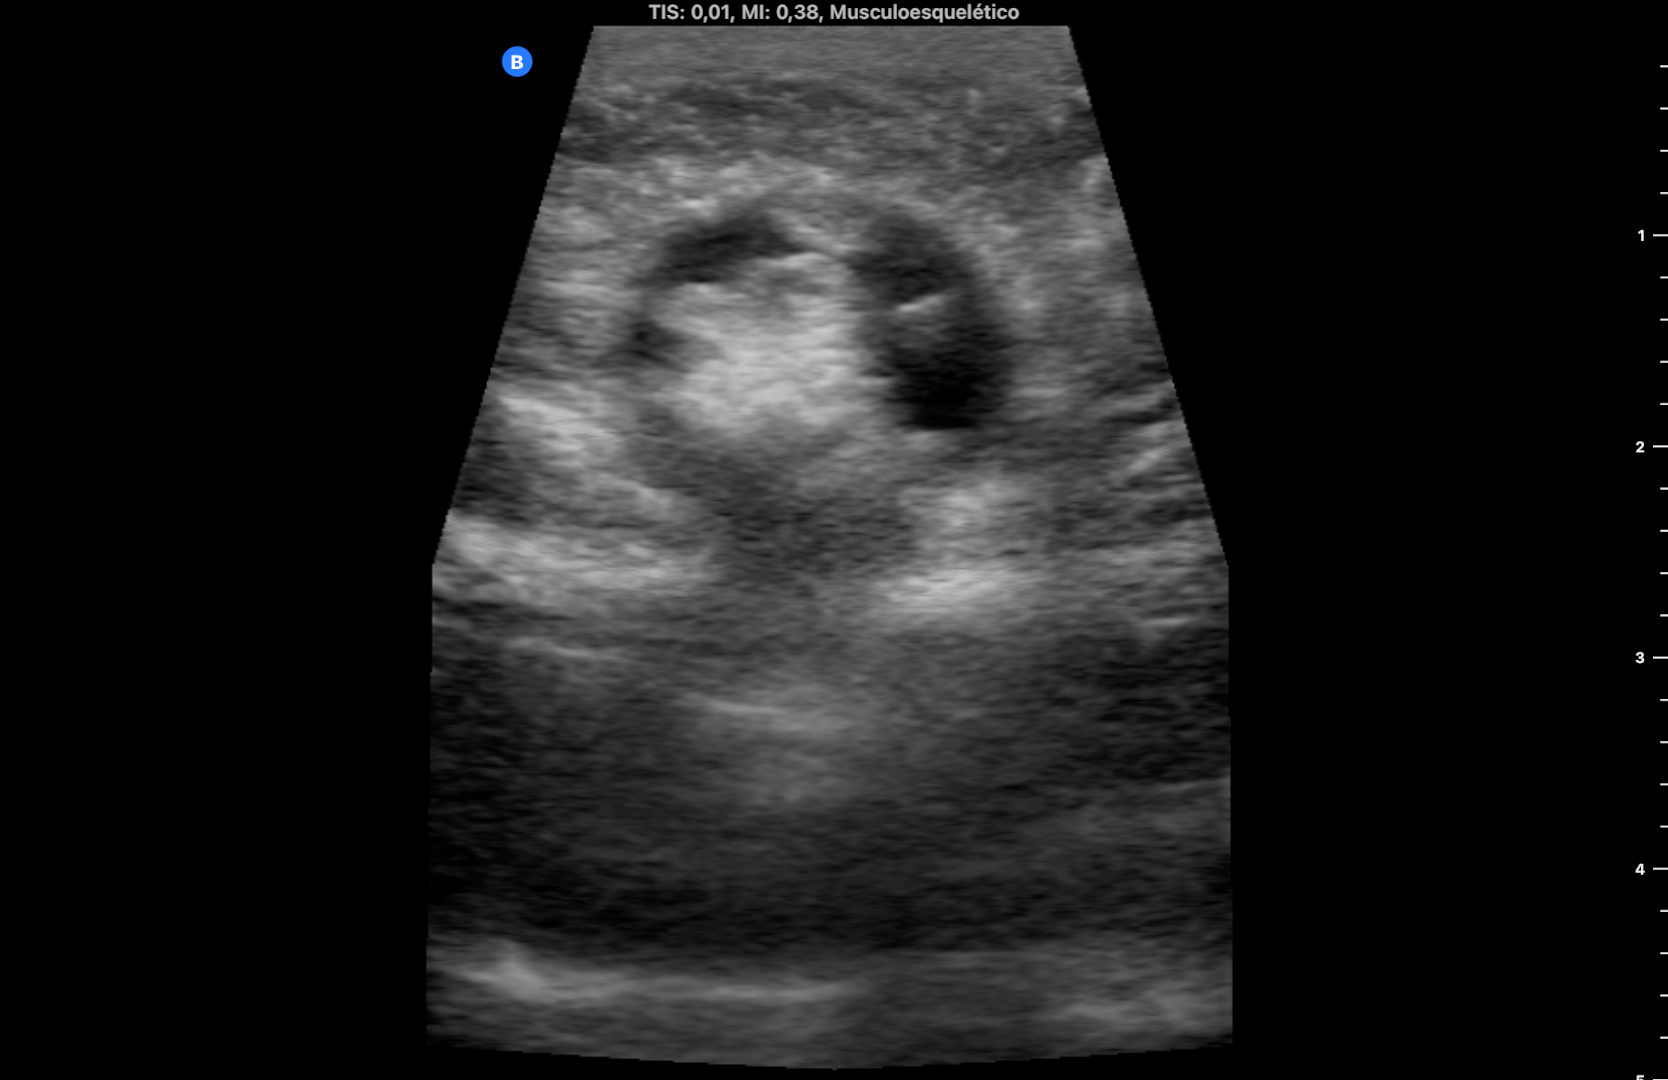

Se utiliza en la misma consulta una sonda portátil con preset de partes blandas, observando una imagen heterogénea redondeada, rodeada de líquido anecogénico a nivel subcutáneo que rompe la línea alba (imagen 1). Durante la exploración se comprime con la sonda en el lugar de la imagen consiguiendo la reducción de la misma y desapareciendo el dolor. La ecografía muestra entonces la discontinuidad de la línea alba con una pequeña protrusión de grasa (imagen 2) (se dispone de vídeos).

Se derivó al Servicio de Cirugía General por circuito preferente, advirtiendo de acudir a Urgencias si volvía a aparecer el bulto y el dolor. Se citó 6 días después persistiendo el orificio herniario de 7,8 mm sin extrusión de asa intestinal (imagen 3).